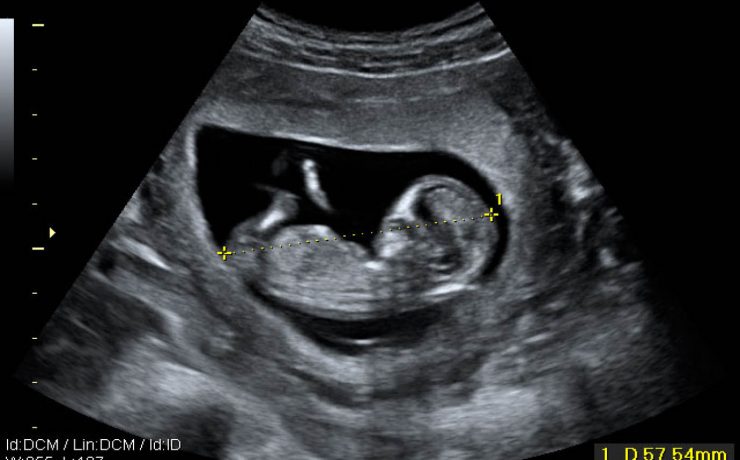

El signo del lirio caído , fue descrito hace más de 40 años en pielografía de eliminación y corresponde al aspecto que adquiere el sistema pieloureteral inferior en un riñón con doble sistema excretor, dado por una pelvis renal de orientación horizontal y cálices que se dirigen discretamente hacia cauda.